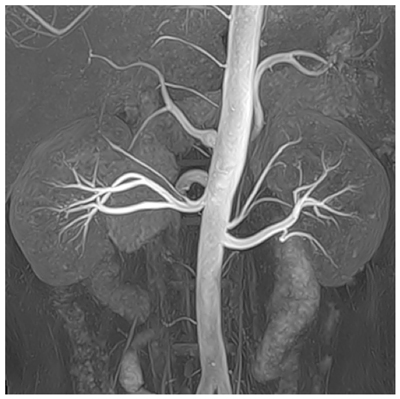

今回は,非造影MRAの臨床応用アプリケーションの中から,1.5テスラ装置に搭載されたTime-SLIP法とDSAやCT,超音波など従来の画像診断法との症例比較検討を重ねることで,非造影MRAの有用性と効果を検証する予定。

腎動脈の非造影MRA画像